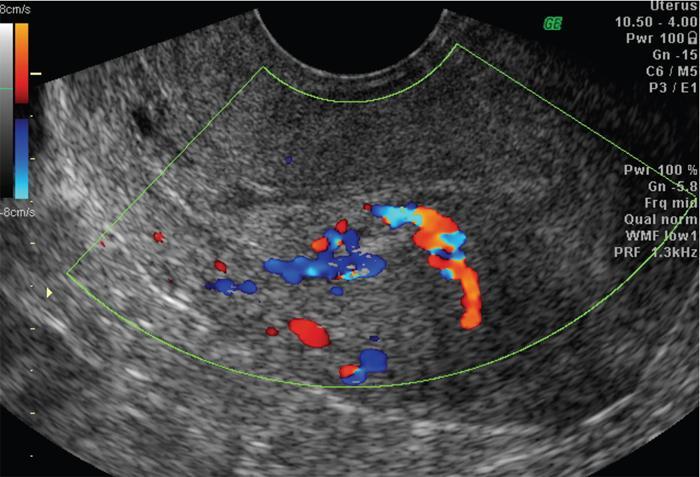

John De Lindsay, Sumathy, Vasumathy, Usha nandhini Ganeshan, N. Sundari ENDOMETRITIS Endometritis is defined as the inflammation of the uterine endometrial layer. Endometritis is frequently observed in the pregnant and postpartum population. Pelvic inflammatory disease (PID) and invasive gynaecological procedures are the most common causes of acute endometritis in nonobstetric population. Endometritis is the most complex asymptomatic and often presents with subclinical form of PID. Ultrasound may reveal minimal particulate endometrial fluid with mildly thickened endometrium showing increased vascularity. Computed tomography (CT) findings include a diffusely bulky uterus due by inflammation, mild fluid distension of endometrial cavity and striking endometrial enhancement in comparison to the adjacent myometrium due to mucosal hyperaemia. ‘Indistinct uterine border’ sign is observed in patients with endometritis, which is defined as the loss of distinction between the uterus and the adnexa. Since it is also observed in the cases of endometriosis or malignancy, it is a nonspecific sign. The age of the patient, clinical presentation, and the biopsy of endometrium helps in differentiating endometritis from other pathologies. UTERINE ARTERIOVENOUS MALFORMATION Uterine arteriovenous malformation (UAVM) is an abnormal connection between the arteries and the veins of the uterine myometrium without an intervening capillary bed. They were first reported by Dubreil and Loubat in 1926. They can be congenital or acquired. Even though UAVMs have varied presentation, uterine bleeding is the most common one. They often follow a pregnancy event. Episodic or occasionally torrential vaginal bleeding can occur. Congestive heart failure secondary to vascular steal can be a rare presentation due to a large UAVM. UAVM is most commonly an acquired condition. Pregnancy has a significant role in their pathogenesis. It is most commonly observed in reproductive age group. UAVMs are frequently observed in the postpartum period, few months after spontaneous miscarriage, surgical evacuation of uterus for miscarriage or medical termination of pregnancy. Infection, inflammation, retained products of conception (RPOC), gestational trophoblastic disease (GTD), gynaecologic malignancies, pelvic trauma and exposure to diethylstilboestrol can also lead to UAVMs. Few cases are also reported in young adolescent and postmenopausal females. UAVMs rarely are congenital and may be also associated with AVMs in other locations. Congenital AVMs Congenital AVMs have a central nidus with multiple feeding arteries and draining veins. In this condition, there is extension of the lesion beyond that uterus and multiple pelvic vessels other than uterine vessels draining into them. That cause of congenital AVMs are thought to be due to failure of embryological differentiation. With the progression of pregnancy, these vessels have the propensity to invade surrounding structures. Iatrogenic Acquired AVMs When the venous sinuses are incorporated into the scars of myometrium after the necrosis of chorionic villi, acquired malformations may arise. In contradiction to congenital AVMs, acquired AVMs multiple fistulous communication between the intramural arteries and the venous plexus. These AVMs may have either dual blood supply or a single supply from the uterine arteries and presents without nidus. Vaginal bleeding caused by pregnancy-related causes must be differentiated from UAVMs. Surgery/evacuation is the appropriate management for the former and the same is contraindicated in the UAVMs and hence an accurate definitive diagnosis is important. Grey-scale ultrasound findings are nonspecific and they are subtle heterogeneity of myometrium with multiple tubular or ‘spongy’ anechoic or hypoechoic areas. In spite of varied presentations such as an intramural uterine, endometrial or cervical mass-like lesions or prominent parametrial vessels, it has minimal mass effect. On colour Doppler, within the myometrium, a region of increased vascularity and most commonly with aliasing is seen. A group of vessels traversing the myometrium running perpendicular to and into the endometrium, from the arcuate vessels, can be seen. It is not specific, as they are also observed in RPOC, GTD, placental polyp and vascular endometrial neoplasm. In pulsed Doppler, multidirectional turbulent flow with intense vascularity can be seen with high peak velocity (mean peak systolic velocity [PSV] = 136 cm/s) and low resistance (mean resistance index = 0.3) flow. The arteries have low pulsatility while the draining veins are pulsatile and show high velocity flow. Magnetic resonance imaging (MRI) offers noninvasive confirmation of the diagnosis of UAVM. T1-weighted and T2-weighted images show multiple serpentine signal voids along the uterine wall, endometrial cavity and parametrium. Contrast-enhanced MR angiography shows intensely enhancing complex serpentine abnormal vessels with early venous return. Catheter angiography can be reserved only for women who require embolization of the AVM. The consent for both diagnostic angiography and therapeutic embolization should be obtained simultaneously to avoid repeat therapeutic procedures. Management of UAVM depends on: UAVM can be treated with medical therapy with hormones, uterine artery embolization or with definitive hysterectomy. Once the diagnosis of a UAVM is confirmed, the treatment option depends on the clinical condition of the patient. The size of the AVM bears no correlation to the need for embolization. Timmerman et al. found that AVMs having PSV of at or above 0.83 m/s, most often requires embolization. Also, the vascular malformation with PSV value below 0.39 m/s does not require embolization. Placental bed subinvolution, enhanced myometrial vascularity (EMV), molar pregnancy or RPOC are the other causes of uterine mass vascular malformations which usually has a mean PSV of 0.52 m/s and does not require embolization. Transcatheter targeted uterine artery embolization is indicated in selected cases, if bleeding persists to a degree that blood transfusions are required to maintain haemodynamic stability or multiple repeated acute hospitalizations. This is preferred over surgical management owing to its immediate minimally invasive and fertility sparing benefits. Gelfoam had been suggested earlier as the material of choice for embolization. Various other embolic materials like polyvinyl alcohol, Histoacryl glue, stainless steel coils, detachable balloons, and haemostatic gelatin are also used nowadays. Normal intrauterine pregnancies after embolization have been reported, proving that an adequate collateral blood supply can develop to support a full-term pregnancy. Gestational Trophoblastic Disease RPOC: Presence of endometrial pathology rather than myometrial origin. FIBROIDS Leiomyomas, also known as fibroids or myomas, are the most common gynaecologic neoplasms, occurring in 20%–30% of women of reproductive age. Symptomatic uterine fibroid accounts for about 30% of hysterectomies performed for women older than 18 years of age and 41% of hysterectomies performed for women from 44 to 64 years of age. Leiomyomas are the benign neoplasms made up of whorled fascicles of smooth muscle and fibrous connective attached to the uterine muscular wall. Even in the absence of true capsule, leiomyomas are well circumscribed and contains a pseudocapsule. Its size is variable, ranging from tiny microscopic to large tumours filling the abdomen. Most commonly, the uterine leiomyomas are seen in the myometrium of uterine corpus. However, it is also seen in the cervix (<5% of cases). On the basis of the location, uterine fibroids are classified as submucosal, intramural or subserosal. This classification is of clinical significance because the symptoms and treatment vary among these subtypes of leiomyomas. Submucosal myomas are further subclassified as 0, I and II depending on the percentage within the endometrial cavity. The first two categories can be removed hysteroscopically (Table 11.15.3.1). Pedunculated leiomyomas are attached to the uterus by a stalk and may be either intracavitary or exophytic (narrower than 50% of diameter of myoma). Rarely, a submucosal fibroid may grow pedunculated and extends into the cervical canal or vaginal canal and its prevalence is about 2.5%. Pedunculated subserosal leiomyomas may undergo torsion, resulting in infarction accompanied by pain. Lateral growth into broad ligament leads to intraligamentous leiomyoma (Table 11.15.3.1). Rarely, a pedunculated leiomyoma may become detached from the uterus (parasitic leiomyoma). Depending on the location, size and number of uterine fibroids, it has varied presentation. Symptoms caused by leiomyomas are classified into three different categories such as abnormal uterine bleeding, pelvic pressure and pain and reproductive dysfunction. Submucosal leiomyomas and intramural leiomyomas are often associated with menorrhagia (Table 11.15.3.1). Because of leiomyoma, uterus may be irregularly shaped and causes symptoms based on their locations. Anterior leiomyomas cause urinary symptoms, whereas the posterior leiomyomas cause constipation. Ureter may be compressed by broad ligament leiomyomas and presents as hydroureter or hydronephrosis. In case of degeneration or torsion of a pedunculated leiomyoma, acute pain may be the presentation. Leiomyomas are an infrequent primary cause of infertility. Malpresentation, pregnancy failures and dystocia are reported. Ultrasound is the first-line imaging modality because it is a cost-effective portable real-time examination that provides good anatomic detail. Leiomyomas appear as a well-defined round or oval hypoechoic solid mass. It is mostly associated with posterior shadowing possibly due to calcifications or interface of the margins of the leiomyoma with the normal myometrium. Degeneration or lipoleiomyoma can be suggested when there is internal echo-poor or hyperechoic foci, respectively. The presence of hypervascularity in a large solitary uterine mass can identify suspicious masses, such as a leiomyosarcoma (LMS). Another study found that there is an increased detection rate of uterine sarcomas while using a cut-off value of 41 cm/s. In the assessment of a uterus enlarged with multiple leiomyomas, ultrasound has FOV limitations. Likewise, it has limited role in the assessment of retroverted uteri, pedunculated subserosal myomas and concomitant adnexal processes. Little has been reported regarding sonographic changes after MR HIFU and uterine fibroid embolization (UFE). Differential diagnosis has been discussed in Table 11.15.3.2. Hyperechoic unlike a myomatous polyp which appears hypoechoic Heterogeneous endometrium with little mass effect Enlarged uterus and a deformed contour are the most common computed tomography (CT) findings. Even though CT is the primary modality for the staging of cancers, it has limitation of reduced contrast resolution for the assessment of focal myometrial masses, and associated with risk of ionizing radiation. Also, in delineating the zonal anatomy for accurate localization of leiomyomas and LMSs, CT is inferior to magnetic resonance imaging (MRI). More often dense or amorphous calcification is seen. Almost exclusively, on plain radiography or CT, these patterns of calcification favours the diagnosis of leiomyoma. Ring-like calcification at the margins of a leiomyoma is a rarely observed pattern, which represents the thrombosed veins. Positron emission tomography (PET)/CT is an ideal modality for the confirmation of malignancy and also helps in detection of metastasis and recurrence. In a small study of patients with histopathologically confirmed uterine sarcoma found that on comparing with the findings of MRI and ultrasound with power Doppler imaging, the results of fluorodeoxyglucose (FDG) PET examinations were 100% positive. However, it has limitations such as increased false-positive rate and reduced widespread availability. MRI appearance of leiomyomas: MRI is considered as the most accurate imaging technique for the detection and localization of leiomyomas. In determining the presence and location of leiomyomas in infertile women before myomectomy, MRI has been shown to be more accurate and sensitive than US or hysterosalpingography. Nondegenerated uterine leiomyomas usually has a typical MRI appearance of (Table 11.15.3.4) well-circumscribed masses with homogeneously decreased T2-weighted signal intensity. TABLE 11.15.3.3 Note: SI, signal intensity; ADC, apparent diffusion coefficient. Compared with that of normal smooth muscle myometrium. Degenerated leiomyomas have varied imaging appearances on T1-weighted, T2-weighted and contrast-enhanced images as described in Tables 11.15.3.4 and 11.15.3.5. Hyaline Oedema *Common *50% cases *Usually peripheral Cystic Myxoid Carneous, red, or UAE associated Calcific Leiomyoma variants (Tables 11.15.3.4 and 11.15.3.6): There are several, such as mitotically active, cellular and atypical leiomyomas, as well as smooth muscle tumours of uncertain malignant potential (STUMP). On histopathological examination, the nondegenerated fibroids are made up of goals of uniform smooth muscles with varied amounts of collagen. Cellular leiomyomas, which are composed of compact smooth muscles cells only with no collagen, will demonstrate increased T2-weighted signal intensity and homogeneous enhancement. There is a greater risk of recurrence in case of atypical leiomyomas and uterine STUMP. The patients who had undergone myomectomy and were found to have atypical leiomyoma, must be under surveillance with an annual pelvic ultrasound or MRI. Since the recurrences may presents as pelvic or abdominal masses or as pulmonary metastases, for all the patients with STUMP lesions, routine physical examinations, including pelvic examinations and the baseline CT of the chest, abdomen and the pelvis are recommended for every 6 months for 5 years and then annually thereafter. In addition, prompt re-exploration and staging is recommended for patients with STUMP who have undergone a morcellation myomectomy. An aggressive imaging surveillance is considered, when the disease is present. Atypical leiomyomas and STUMPs routinely express progestin receptors; however, because of the low recurrence rates, there is no role for adjuvant hormonal therapy. Atypical uterine masses can be treated surgically with hysterectomy or myomectomy. Histologic subtype Cellular leiomyoma Round or oval Single large lesion with absence of coexistent adenomyosis Responds to GnRH analogues Cured with surgery No need for follow-up Lipoleiomyoma Well defined: round or oval STUMP Round or oval Intense surveillance Note: SI, signal intensity; ADC, apparent diffusion coefficient; UAE, uterine artery embolization; STUMP, smooth muscle tumours of uncertain malignant potential. Being a benign neoplasm, fibroids usually have a pushing border and rounded edges. But, specific types of fibroids represent growth pattern variations, such as intravenous leiomyomatosis, metastasizing leiomyoma, diffuse leiomyomatosis and peritoneal disseminated leiomyomatosis. Retroperitoneal growth and parasitic growth are the other atypical growth patterns. Even cervical and vaginal leiomyomas may show growth pattern. It is important to note that adenomyosis and focal myometrial contraction can coexist and distinction is important at preprocedure imaging (Table 11.15.3.7).